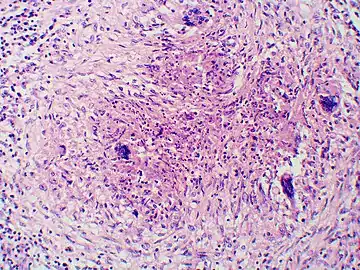

Additional images

Granuloma with early suppuration. Fungal organisms difficult to recognize at this low magnification.